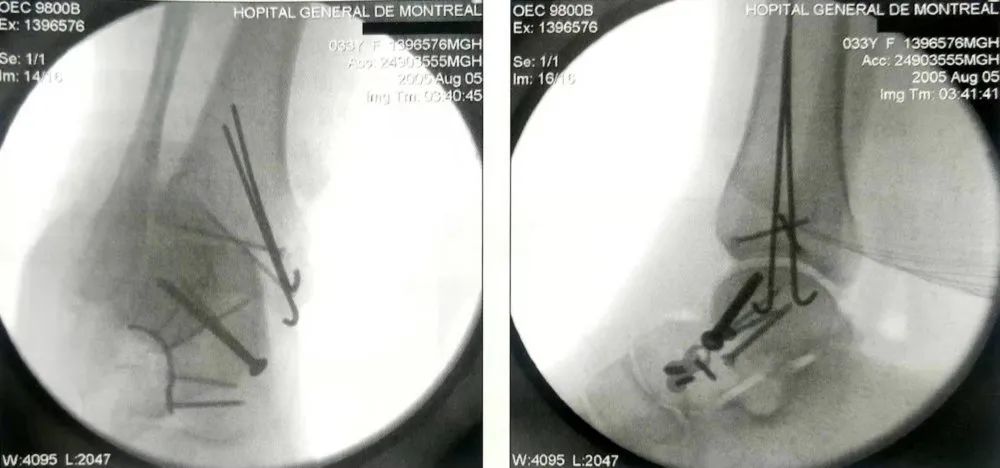

距骨颈骨折

骨折后固定的斜位片(A)及侧位片(B)

距骨颈骨折合并典型的内侧粉碎,外侧用2.7mm钛合金板,内侧用两枚固定钉,分别为3.5mm和2.7mm,复位后固定。